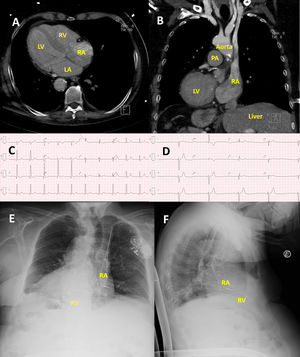

Dual-chamber pacemaker implantation in a patient with situs inversus totalis with dextrocardia. (A) Axial view and (B) coronal view of thoracic computed tomography scan showing mirror-image anatomy with dextrocardia, normal atrioventricular and ventriculoarterial connections, and right-sided liver. (C) Baseline ECG showing sinus rhythm with right bundle branch block and left posterior fascicular block. (D) ECG performed after syncope revealing trifascicular block with second-degree atrioventricular block Mobitz type II. (E) Posteroanterior and (F) lateral chest radiographs demonstrating left-sided pacemaker generator with transvenous leads directed toward the right atrial appendage and right ventricular apex, confirming successful pacemaker implantation. LA: left atrium; LV: left ventricle; RA: right atrium; RV: right ventricle; PA: pulmonary artery.

The chest X-ray showed situs inversus, leading to a thoracic computed tomography scan to confirm the venous anatomy. The computed tomography scan confirmed the complete mirror-image anatomy and excluded venous drainage abnormalities (Figure 1A and B). Despite the unusual anatomy, a dual-chamber pacemaker was successfully implanted in the left prepectoral region via ultrasound-guided axillary vein puncture. Atrial and ventricular leads were positioned in the right atrial appendage and right ventricular apex, respectively (Figure 1E and F), with appropriate electrical parameters.

We present the case of a 79-year-old man with situs inversus totalis who was admitted to the emergency department for syncope caused by high-grade atrioventricular block, with no identifiable reversible causes. Transthoracic echocardiography revealed preserved ejection fraction and no valvular disease.